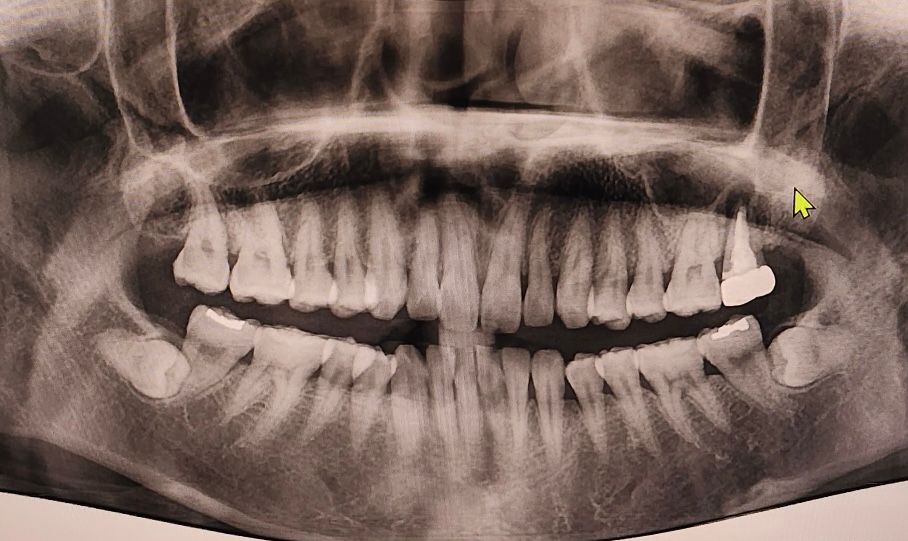

뿌리염증으로 발치후 임플란트 식립과 뼈이식 시기는?

5년전 신경치료하고 크라운했던 위쪽 맨끝 어금니에 뿌리염증이 생겼고

염증이 큰편이여서 재신경치료는 어렵다고해서 고민하다가 하루전에 발치했습니다.

저정도 상태라면 발치하시고 3개월정도 기다리시면 잇몸뼈가 찰꺼 같습니다. 그떄 가셔서 뼈이식 여부를 확인하셔도 될것같습니다.

뼈 상태를 보고 식립할 수 있으면 빨리 합니다. 염증이 컸던 상태면 뼈이식은 필요합니다.